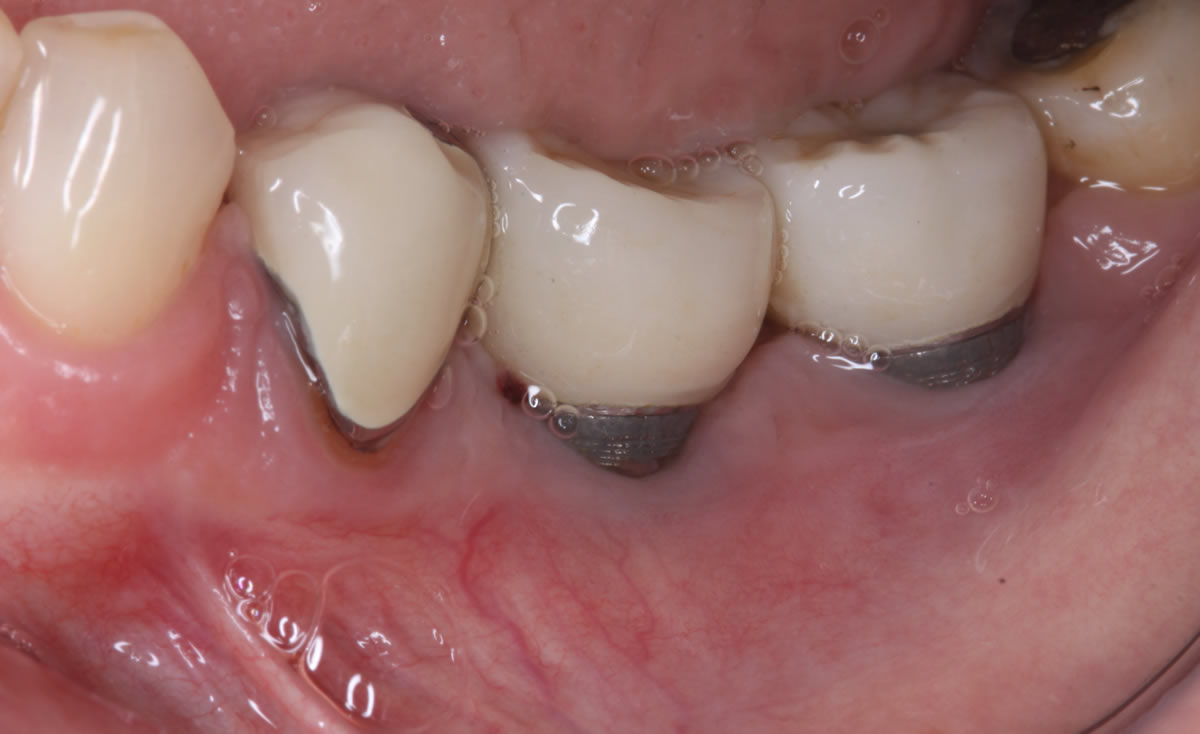

Con la introducción de los implantes en la práctica odontológica habitual, ha aparecido una nueva patología inflamatoria confinada a los tejidos de soporte peri-implantarios: la periimplantitis, que puede llevar al fracaso de los implantes en función.

La periimplantitis es un «proceso inflamatorio que afecta a los tejidos que rodean un implante osteointegrado en función, y que produce una pérdida de soporte óseo»

Otra definición de periimplantitis sería la pérdida de hueso periimplantario detectable en la radiología combinado con lesión inflamatoria de tejidos blandos, combinadas o no con supuración y profundidad de sondaje a 6 mm.